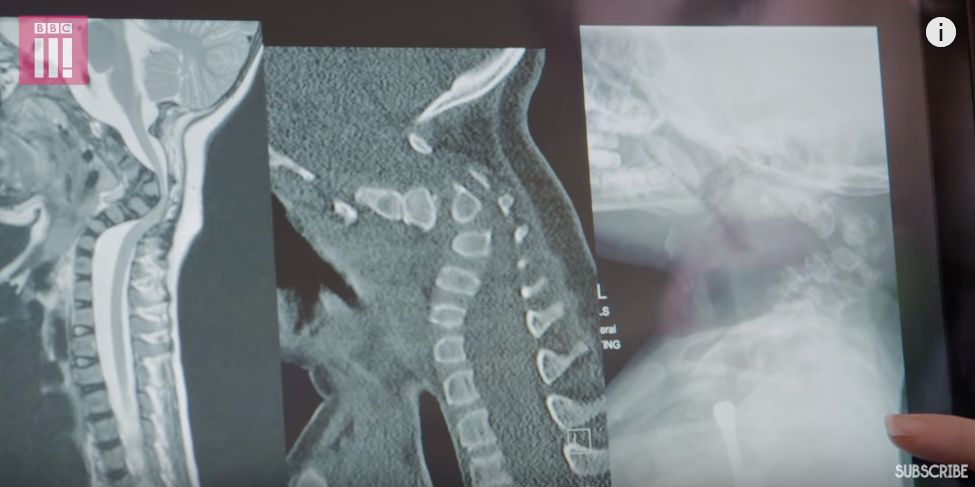

这是一位 III 型 OI 患者

她的颈部非常脆弱

必须依靠颈托支撑着

图片来源:BBC

对于这个小女孩

如果离开颈托

可能会是致命的危险